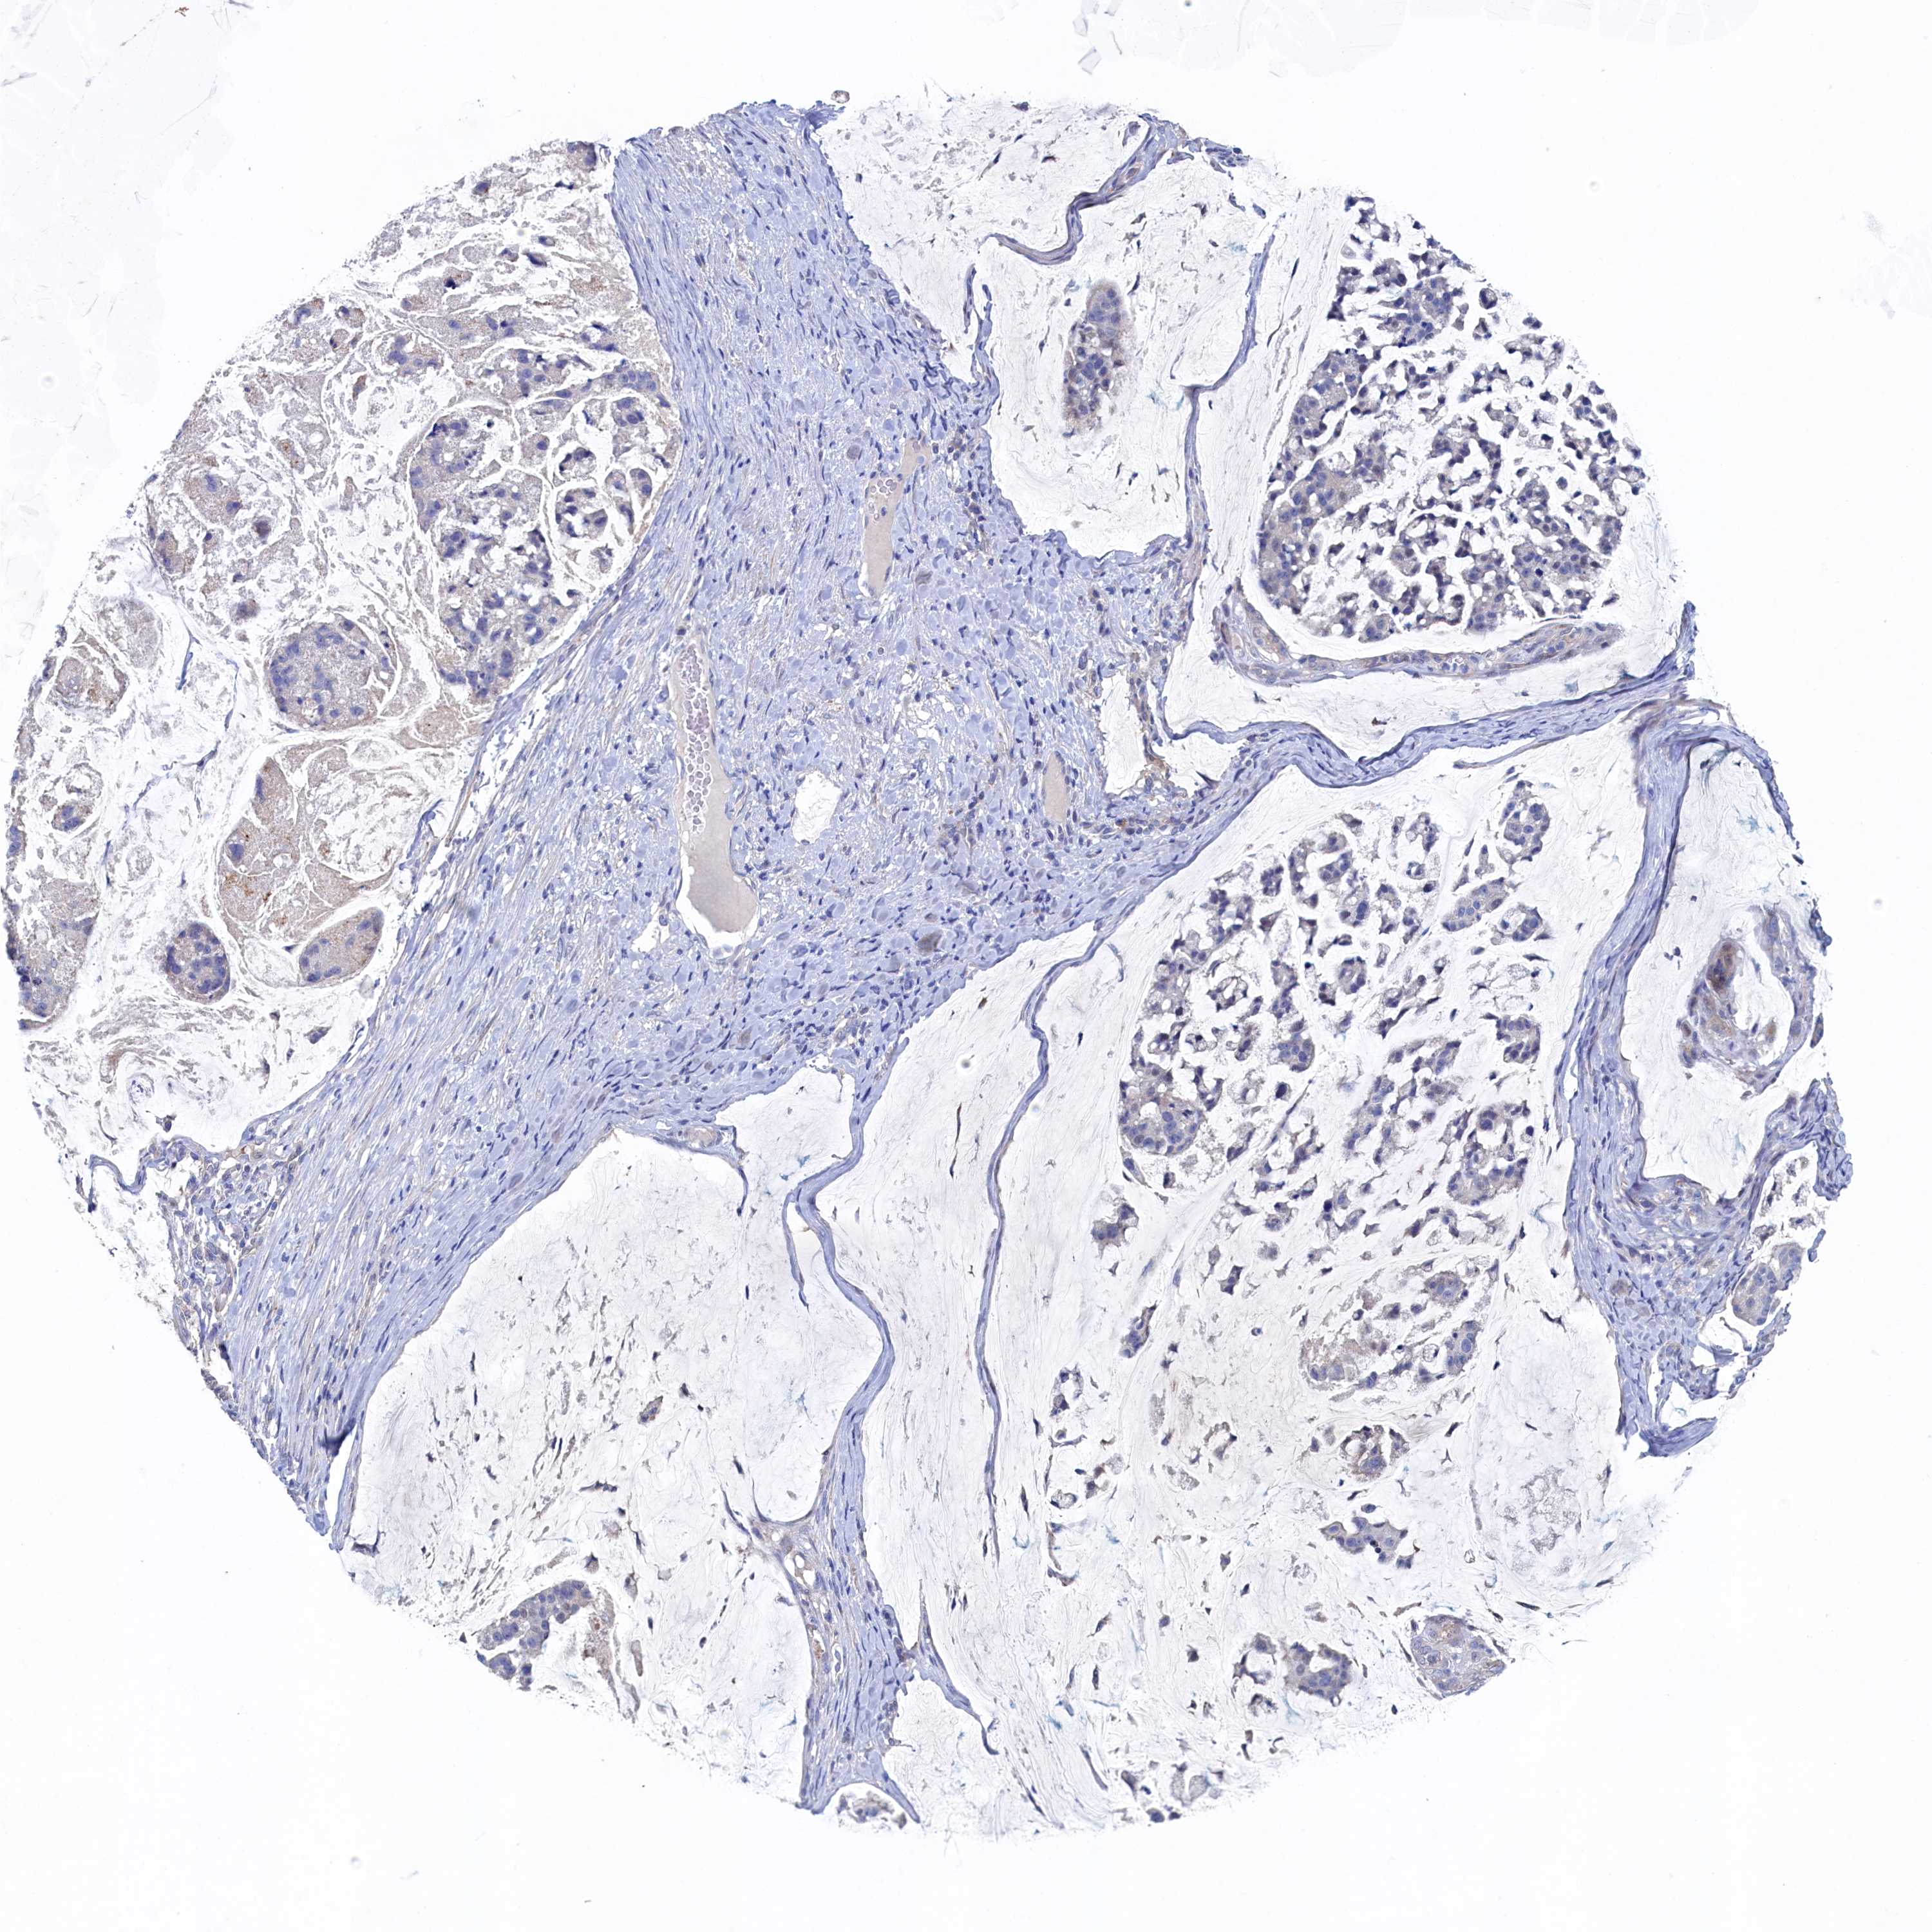

STOMACH CANCER - Protein expressioni

A mouse-over function shows sample information and annotation data. Click on an image to view it in a full screen mode. Samples can be filtered based on level of antibody staining by selecting one or several of the following categories: high, medium, low and not detected. The assay and annotation is described here.

Note that samples used for immunohistochemistry by the Human Protein Atlas do not correspond to samples in the TCGA dataset.

Antibody stainingi

Antibody staining in the annotated cell types in the current human tissue is reported as not detected, low, medium, or high, based on conventional immunohistochemistry profiling in selected tissues. This score is based on the combination of the staining intensity and fraction of stained cells.

Each image is clickable and will lead to virtual microscopy that enables deeper exploration of all samples and also displays staining intensity scores, fraction scores and subcellular localization as well as patient and tissue information for each sample.

Antibody HPA039908

Antibody HPA040774

Staining

High

Medium

Low

Not detected

Intensity

Strong

Moderate

Weak

Negative

Quantity

>75%

75%-25%

<25%

None

Location

Nuclear

Cytoplasmic/membranous

Cytoplasmic/membranous,nuclear

Adenocarcinoma, NOS

Adenocarcinoma, High grade